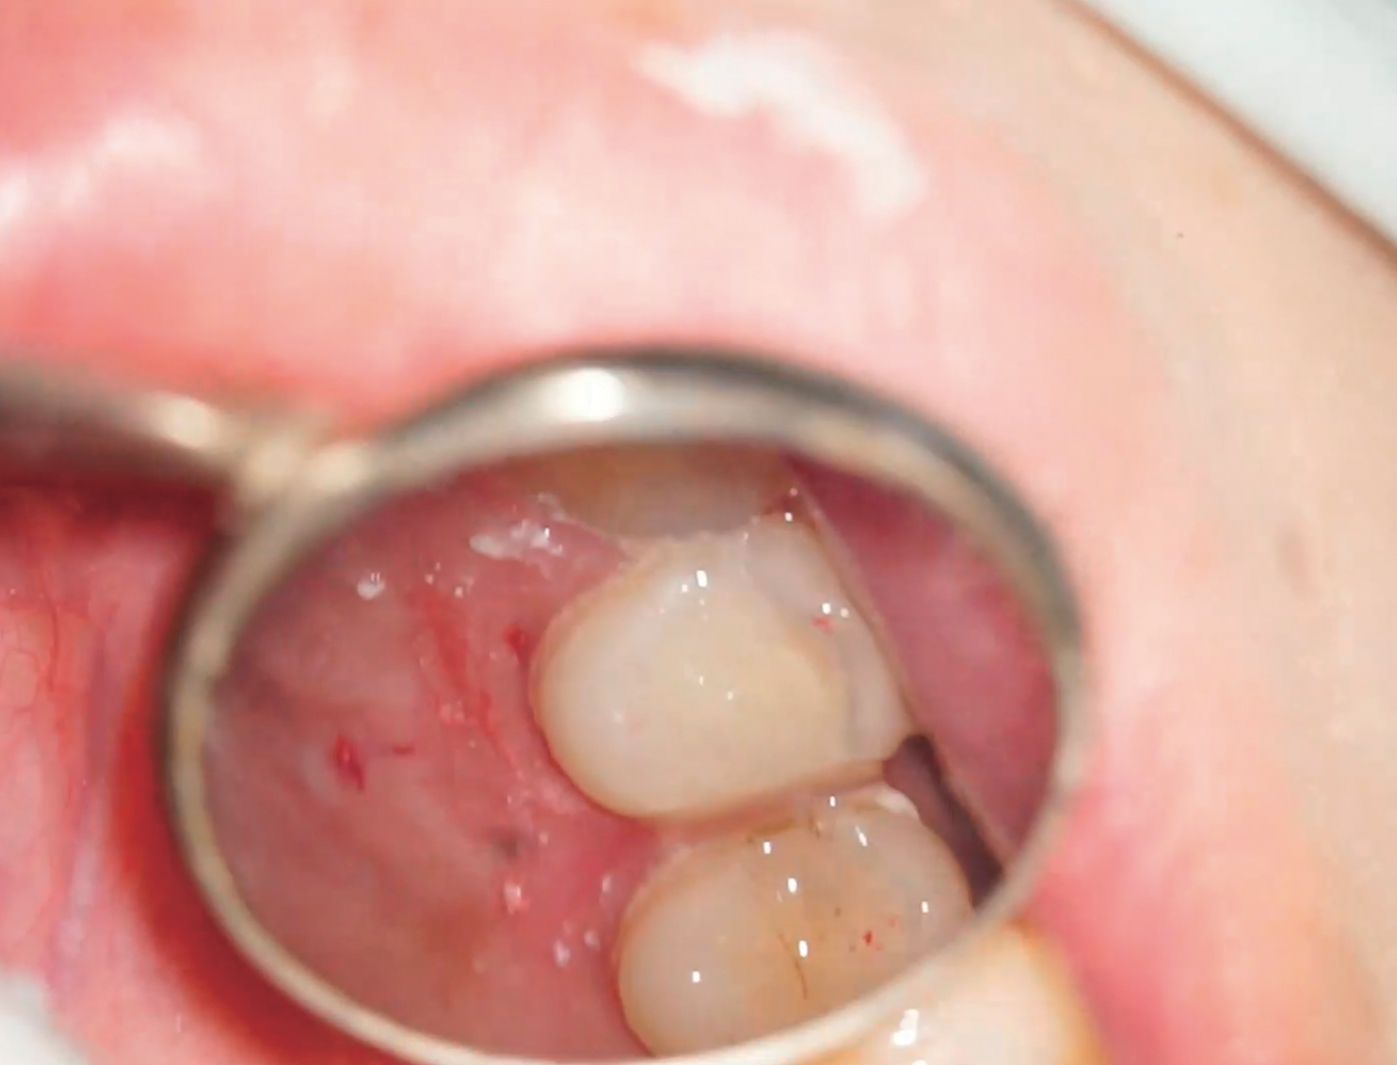

支台築造前の接着処理終了時。遠心の歯質が喪失しており、側方ガイド歯のため遠心壁側にファイバーを設置することを予定した。

アンジェラスホワイトポスト1.1mmを設置。歯質保存のためにポストスペースは形成していない。

支台築造終了時。コア部分には別のコアマテリアルを使用している。

ラバーダム除去後。後日支台歯形成を行い、暫間冠を作製予定。